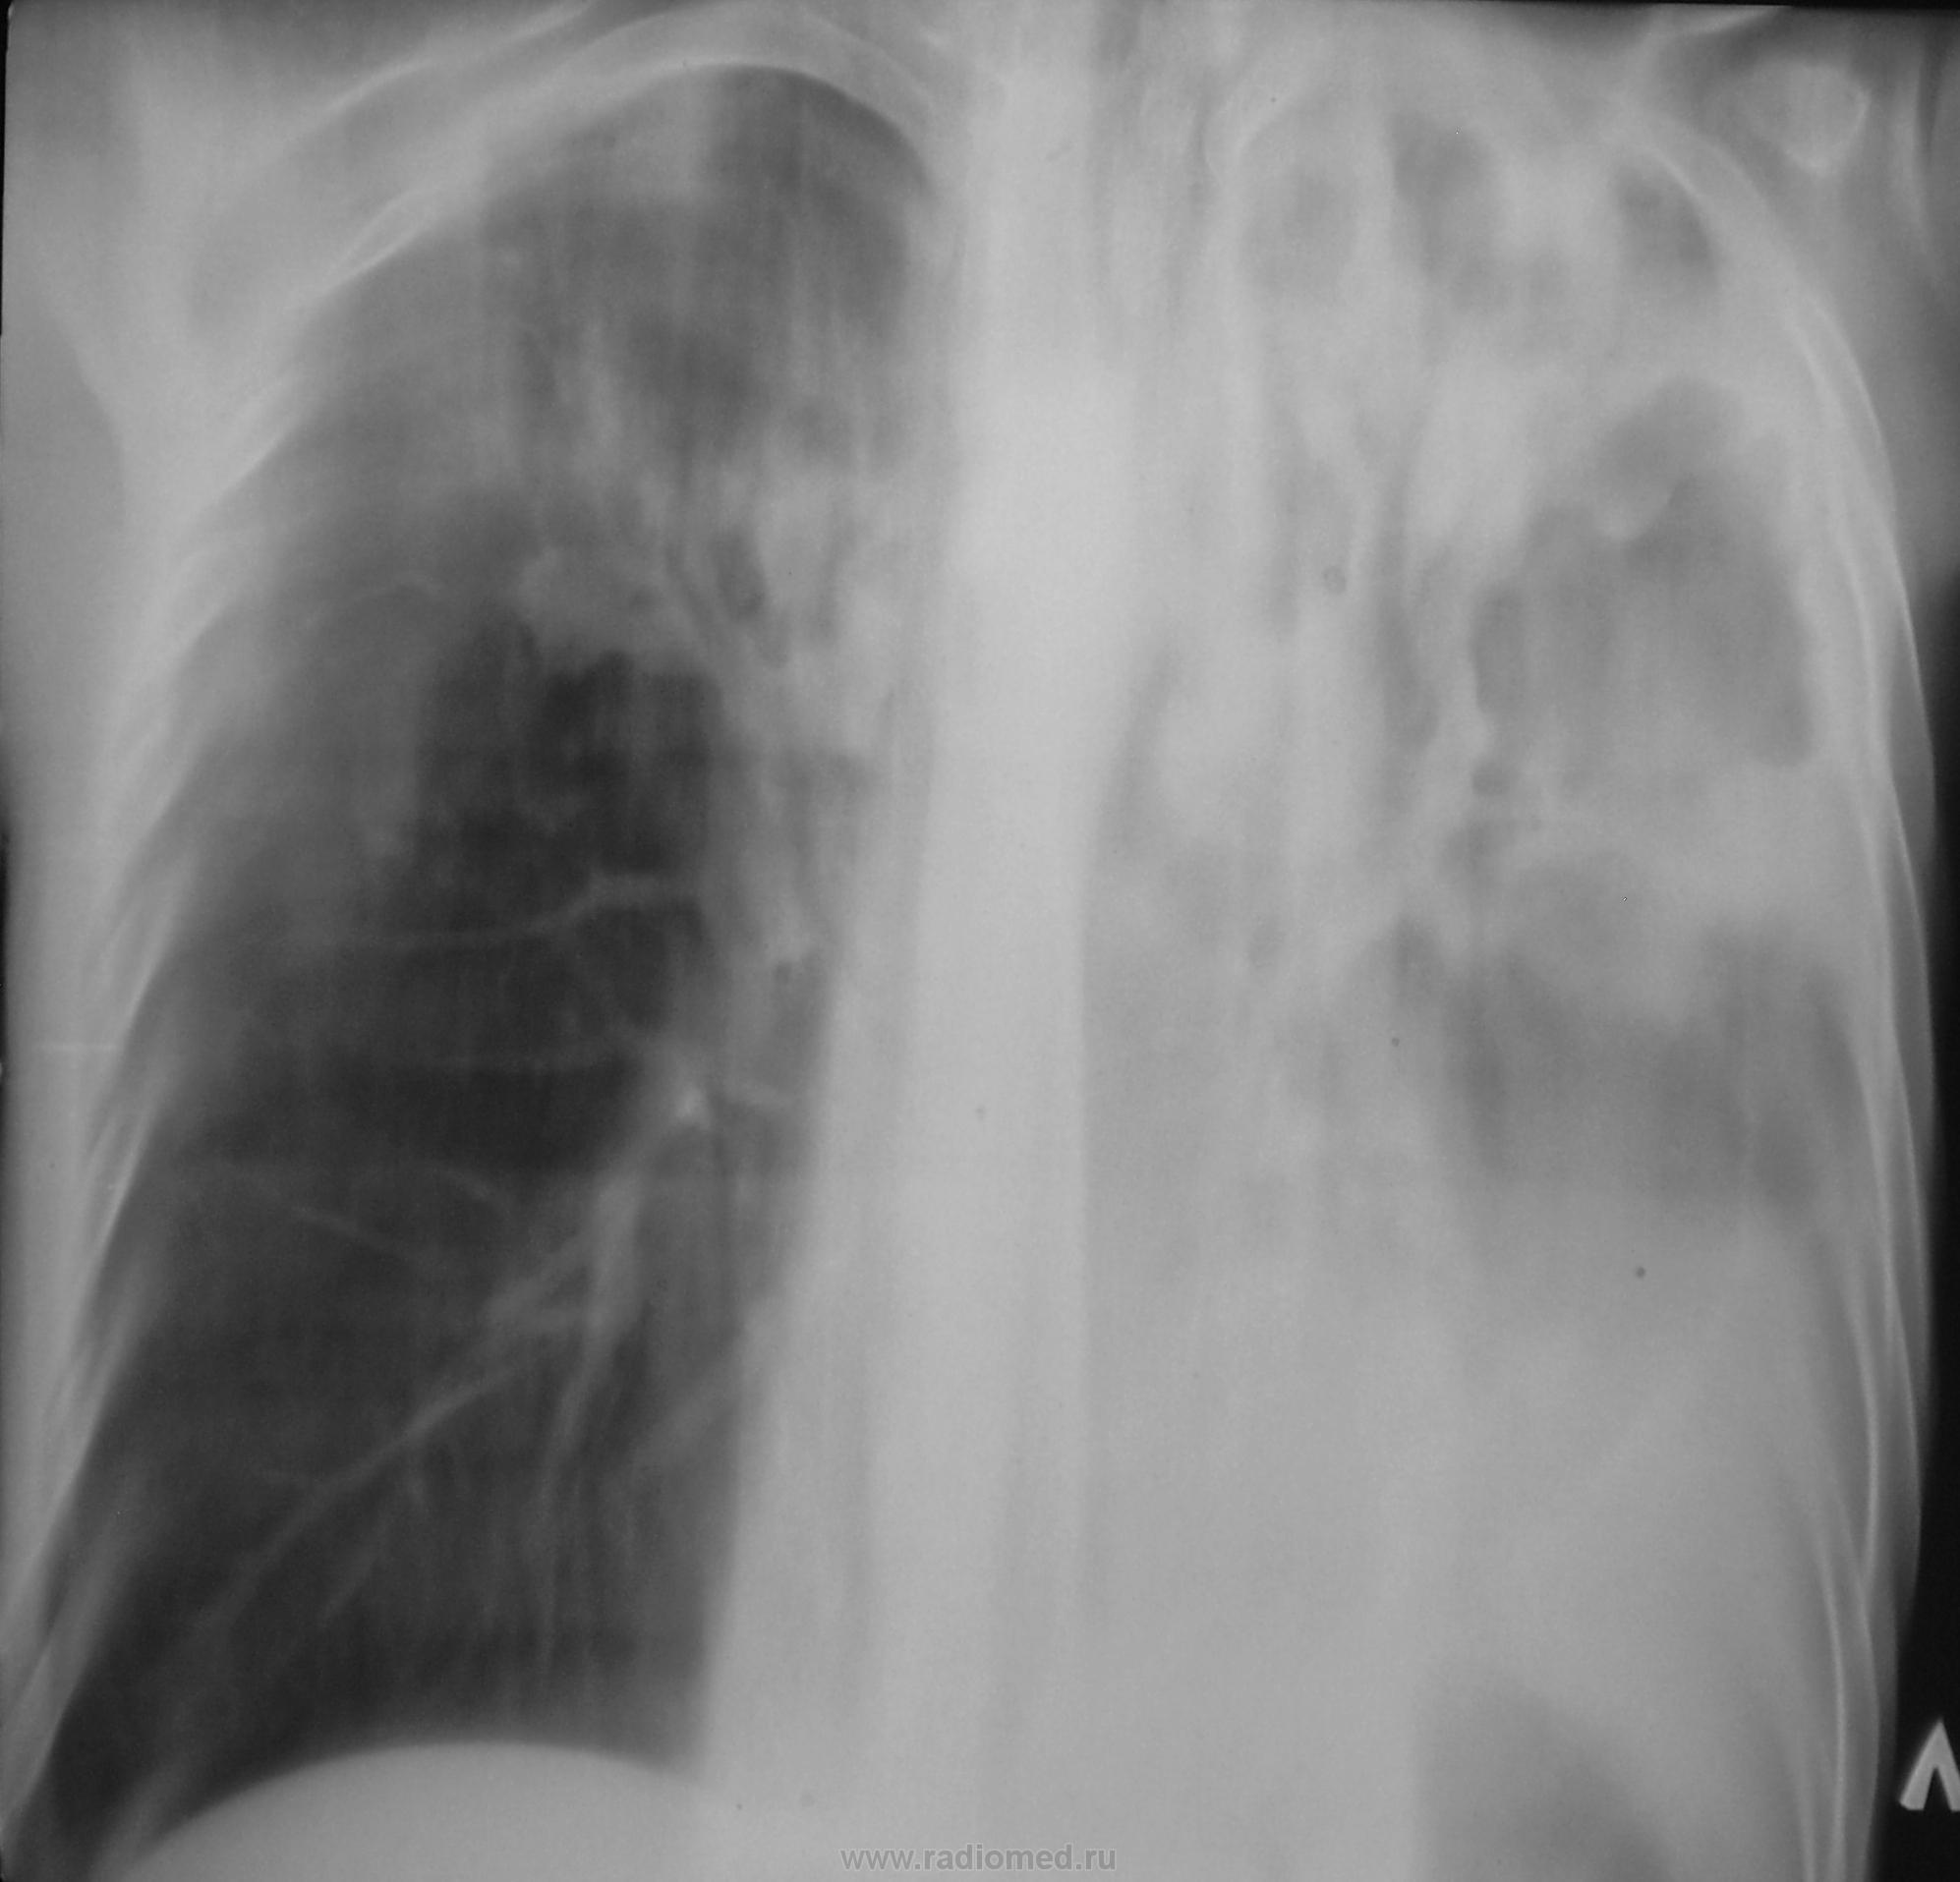

Было высказано продположение о наличии специфического процесса. Была рекомендована консультация фтизиатра. Однако, обстоятельства распорядились в другом векторе. Пациент был госпитализирован в хирургическое отделение был пунктирован, проведено противовоспалительное лечение... и через две недели был назначен рентген-контроль.

После проведенного исследования вновь, повторно была рекомендована консультация фтизиатра. Однако, фтизиатры патологию своей не признали.

Прошел год, пациент значительно потерял в весе, температура около 38 градусов, кашель с мокротой и был доставлен в рентгеновский кабинет на носилках.

"Ой"! Воскликнули фтизиатры, это наше! На носилках пациент был срочно госпитализирован в областную туб больницу в тяжелом состоянии. Лечение, со слов фтизиатров, было не легким, так сказать - "на грани", пациент был прооперирован.